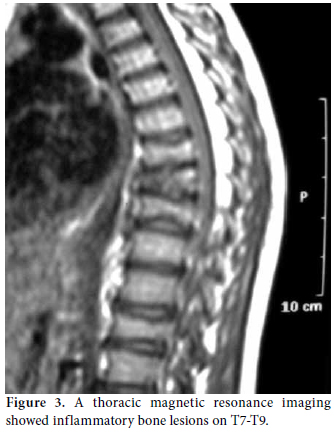

A 10-year-old boy was referred to the Pediatric Rheumatology Unit at the University Hospital Federal University of Pernambuco, Recife in 2008 with a fiveyear history of intermittent pain in his left clavicle, right hip, ankles, and dorsal spine. In 2006, he was admitted to the Pediatric Unit complaining of back pain, fever, and a mass over his left clavicle. Blood tests showed a C-reactive protein (CRP) level of 24 mg/dl and an erythrocyte sedimentation rate (ESR) of 39 mm/h. A chest X-ray confirmed the mass over his left clavicle (Figure 1). Septic osteomyelitis was diagnosed, although his blood and bone cultures were negative. A course of an empirical antibiotic (cephalothin) and NSAIDs was prescribed. He was later referred (after one year) to the Orthopedic Unit where a thoracic computed tomography (CT) scan showed the volume of the left clavicle had increased due to an area of hyperostosis mixed with osteolysis. Hence, the antibiotic was changed to ciprofloxacin for three months. As there was no improvement, he was referred to the Pediatric Rheumatology Unit, where a tuberculin test and ANA were negative. A bone scan showed an increased technetium-99m (99mTc) radioisotope uptake at the left clavicle, ankle, sacroiliac joints, and T8 thoracic disc (Figure 2). Magnetic resonance imaging (MRI) demonstrated multiple inflammatory lesions between the T7 and T9 disks (Figure 3) and in the left clavicle and left ankle (Figure 4), thus confirming the findings on the bone scan and thorax CT. The results of the histological analysis of a bone biopsy were compatible with aseptic chronic osteomyelitis (Figure 5). No infection was identified by lesion or blood culture, and no malignancy was detected by imaging; hence, the possibility of CRMO was raised. An aggressive treatment with NSAIDs, alendronate 70 mg/week, methotrexate 15 mg/week, and infliximab 5 mg/kg was initiated due to the severity of the case and the delay in diagnosis. After the third infusion of infliximab, the boy became free of pain. His ESR and CRP levels were normal, and a bone scan showed a tiny uptake at the left clavicle. It should be noted that the patient and his family gave their consent for any treatment provided at the Pediatric Rheumatology Unit.

A bone biopsy is necessary for the differential diagnosis of CRMO in order to exclude malignancy and infection, and pyogenic osteomyelitis, if found, is a reliable indicator of this disease. Usually an extensive microbial investigation (including tissue culture and serology) should be conducted since treatment with antibiotics is ineffective. However, improvement in patients treated with azithromycin has been reported, but this can be attributed to its anti-inflammatory effect.[14] The biopsy of the clavicle in our case showed a chronic inflammatory reaction like that of a foreign body granuloma.